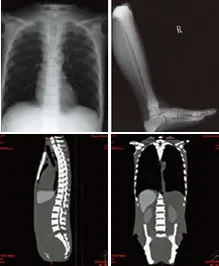

Patient positioning:Right shoulder rotates side ways, abducting to a horizontal position.Left shoulder rotates forward, up to a horizontal position. Elbows bend inward to approx. 90 degrees. Hip joints rotate forward up to 90 degrees, then rotate outward up to 45 degrees, respectively. Knees bend to approx. 90 degrees. The phantom can be held in the supine frog leg position. The limbs and head are detachable at joints and neck for wider applications. The head supporter facilitates various head positions. Anatomy:

Phantom size:approx. 165 cm heightPhantom weight:approx. 50 kgPacking size:approx. 85 X 60 X 44, two-packPacking weight:approx. 80 kg |